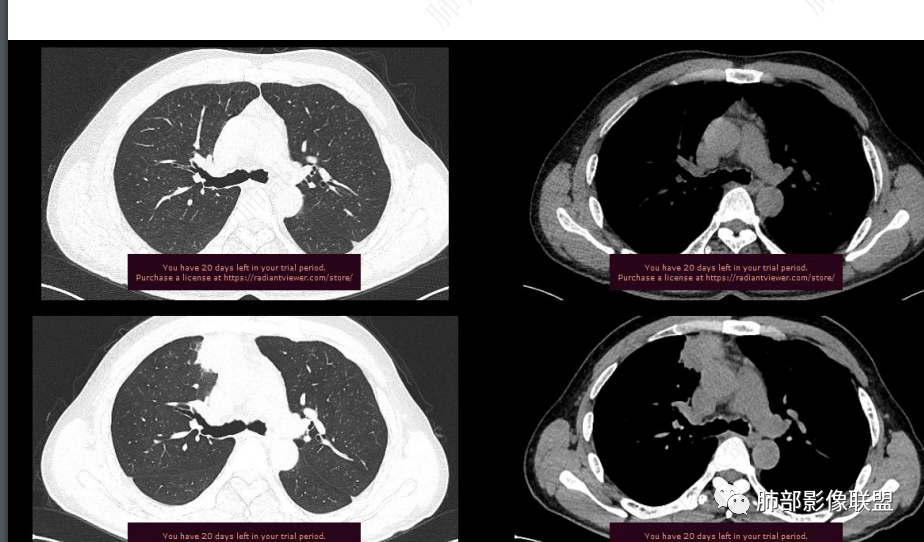

平扫图像

增强图像

CT值信息

1.中年男性,临床发热,症状较轻,中长病程,炎性指标轻度增高。

2.右肺上叶纵隔旁新发实性密度病灶,密度均匀,轻度强化,未见空洞、液化坏死及钙化,血管穿行自如,支气管进入后狭窄截止。灶周磨玻璃影边界不清,病灶未见明显分叶毛刺,平直、轻度收缩、周围偶见结节影,但未见树芽征。注意纵隔胸膜侵入或突入比较明确。纵隔淋巴结轻度增大。

4.肝脏病灶没有假包膜,没有动脉早期强化,没有肝硬化,未见扩张胆管,未见环形强化,也未显示靶征,缺乏肝细胞肝癌、胆管细胞癌、转移癌或肝脓肿特征。